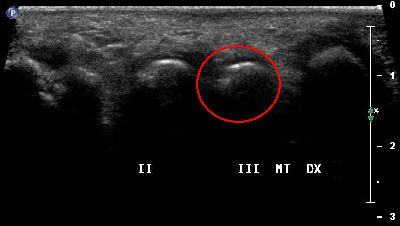

Sesamoide accessorio secondo dito (img. 01) Sesamoide accessorio secondo dito (img. 01)